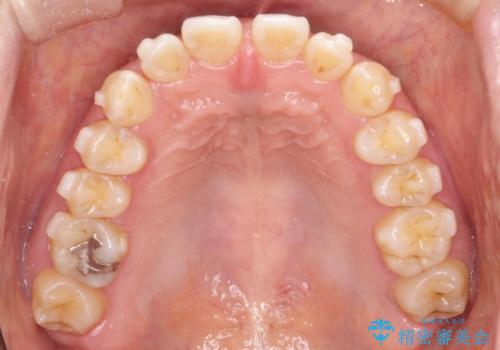

【インビザライン】前歯のすきまを閉じたい

- 前歯の隙間を主訴に来院されました。

インビザライン にて治療を行い、歯並びを改善することができました。